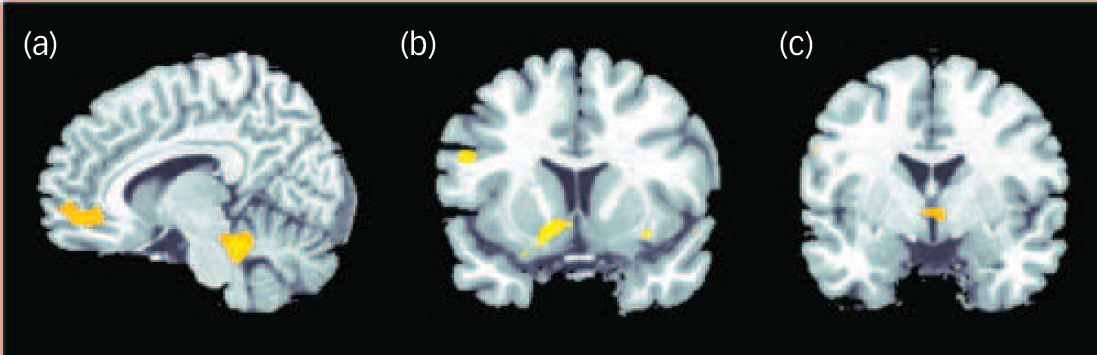

The positive correlation between degree of radial diffusivity extracted from the temporal cluster showing an increased diffusivity in the schizophrenia group and neural activation in association with decision-making under maximum uncertainty revealed no significant results. The negative correlation yielded significant results in a network containing inferior frontal and cerebellar areas, the anterior cingulate, putamen, insula and hypothalamus (Table 2 andFig. 4).

Fig. 3 Significantly stronger activation in the participants in the control group compared with the schizophrenia group in association with decision-making under uncertainty at P<0.01, false discovery rate corrected.

Fig. 4 Negative correlation between degree of radial diffusivity extracted from the temporal lobe cluster showing a difference in diffusivity between the groups and neural activation in association with decision-making under uncertainty in the schizophrenia group.

Significant effects at P<0.001 uncorrected were detectable in the cerebellum and anterior cingulate cortex (a), insula and putamen (b) and hypothalamus (c).